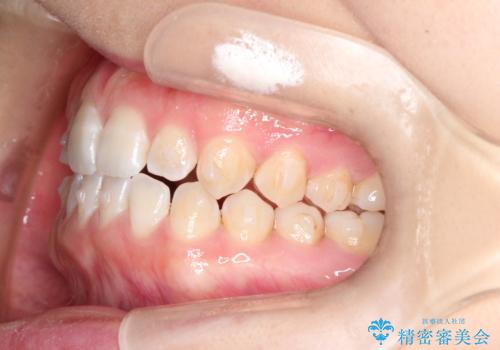

前歯の隙間を閉じたい インビザラインによる矯正

- 上下の前歯に隙間があるとのことで来院されました。

インビザラインにて隙間を閉じる矯正を行いました。

使用時間を守っていただけたので、比較的スムーズに矯正を終了することができました。